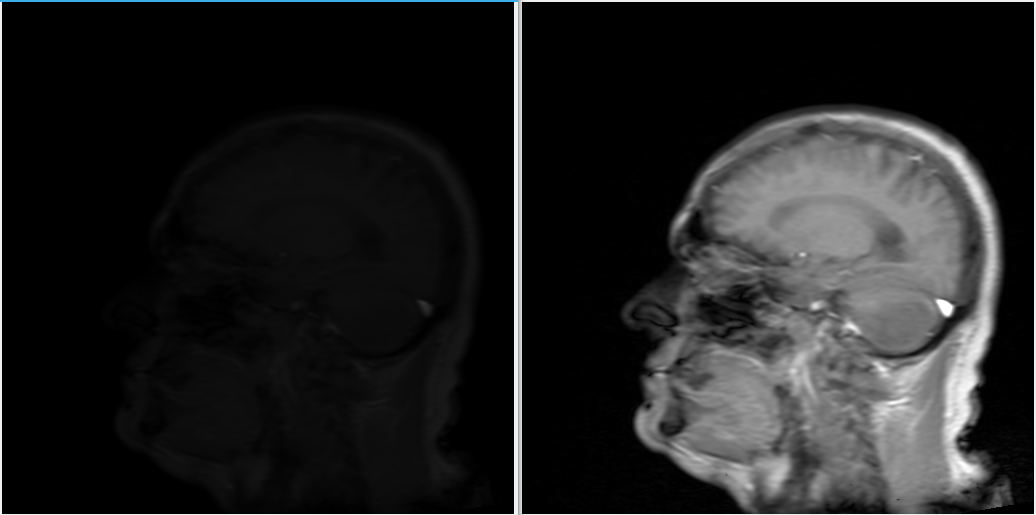

ImageMagick 知道,因此当弹出对话框询问使用什么打开文件时,您可以直接输入 display 并查看您的图像。我很快发现我需要向命令添加 -normalize,因为这些灰度图像的比例非常大,即使所有像素可能都处于比例的低端。下面的示例显示了应用 -normalize 之前和之后的同一图像。

同一图像,应用“normalize”命令之前和之后